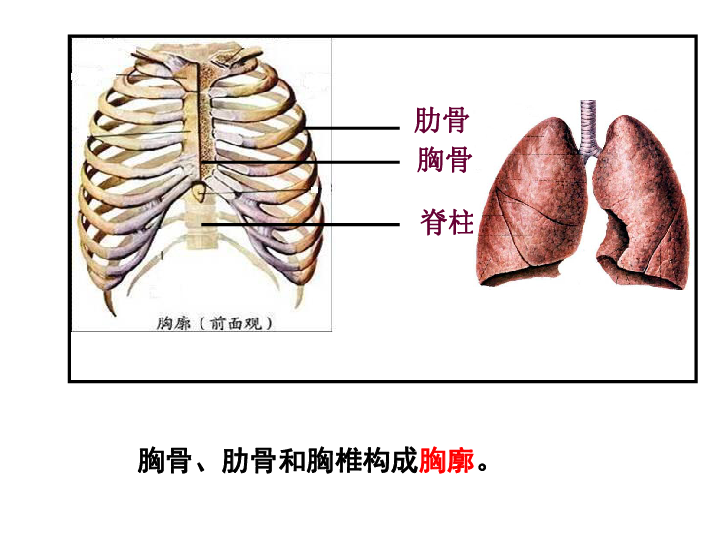

第四节 肺尖 肺 肺尖 肺底(膈面) 肺的外形 前缘 下缘 肋面 内侧面

所有分类 初中教育 理化生 发生在肺里的气体交换动画ppt 一,肺的位置

发生在肺内的气体交换,第三章人体的呼吸,,肺的位置,,,位于胸腔内